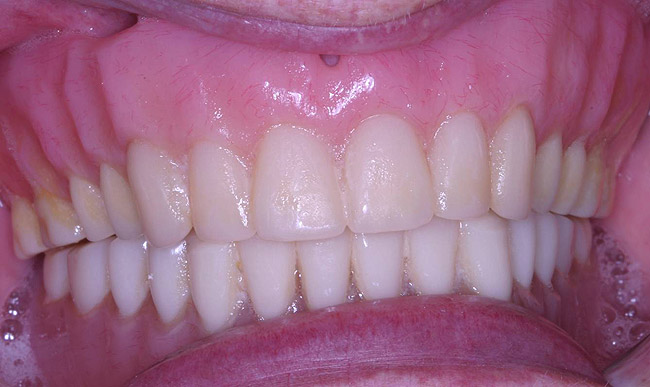

Figure 14  Retracted view of try-in.

Figure 14

The laboratory then fabricated a light-cured, stabilized base plate on which anterior and posterior teeth were set using the silicone putty mold made previously and waxed up to final contour and delivered to the office. The upper denture was tried in and a visual examination was performed to certify function, esthetics, phonetics, and patient/clinician satisfaction (Figure 14). The denture was sent back to the laboratory for final processing with the Ivocap Denture System (Ivoclar Vivadent North America, Amherst, NY). The prosthesis was trimmed and polished to high luster to prepare for final insertion (Figure 15). Additionally, Massachusetts requires denture labeling with a patient identifier (wearer's name, driver's license number, or Social Security Number, etc) for forensic purposes, and this was exacted according to state law.28